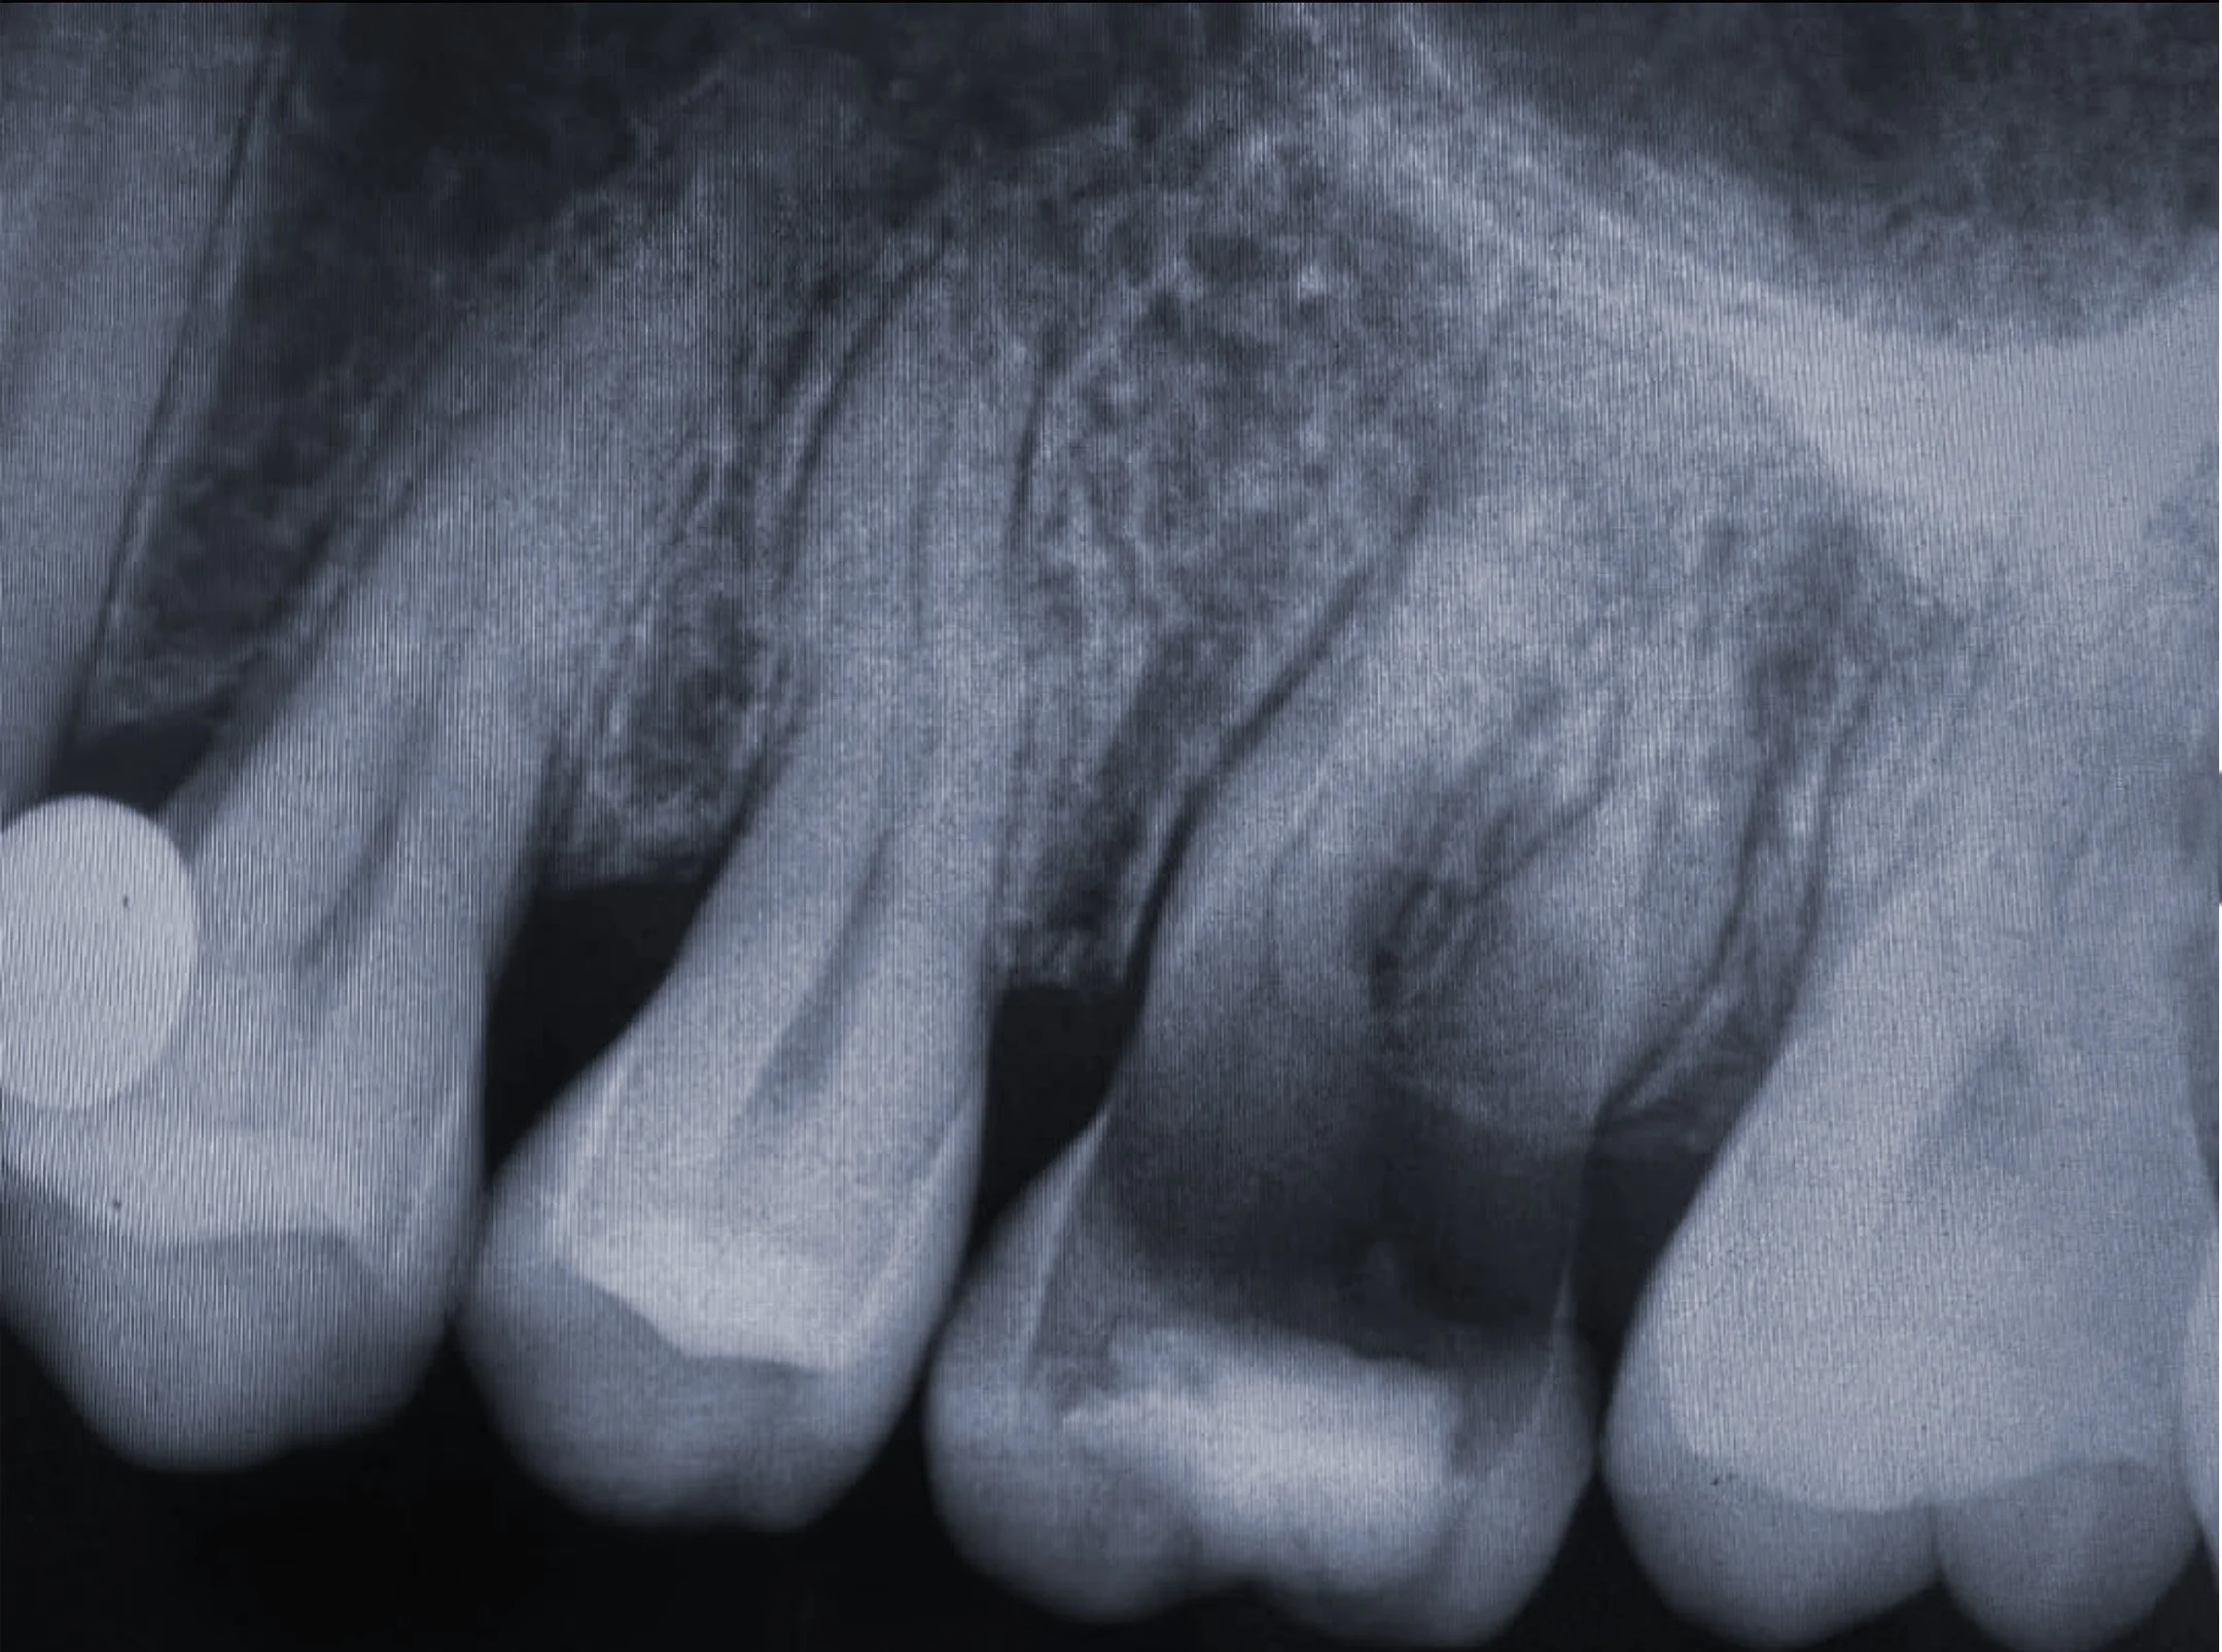

Clinical Studies

These cases illustrate the precision, evidence-based technique, and collaborative approach that guide every procedure in my practice. Each example demonstrates how careful planning and minimally invasive methods can restore health, stability, and long-term function.